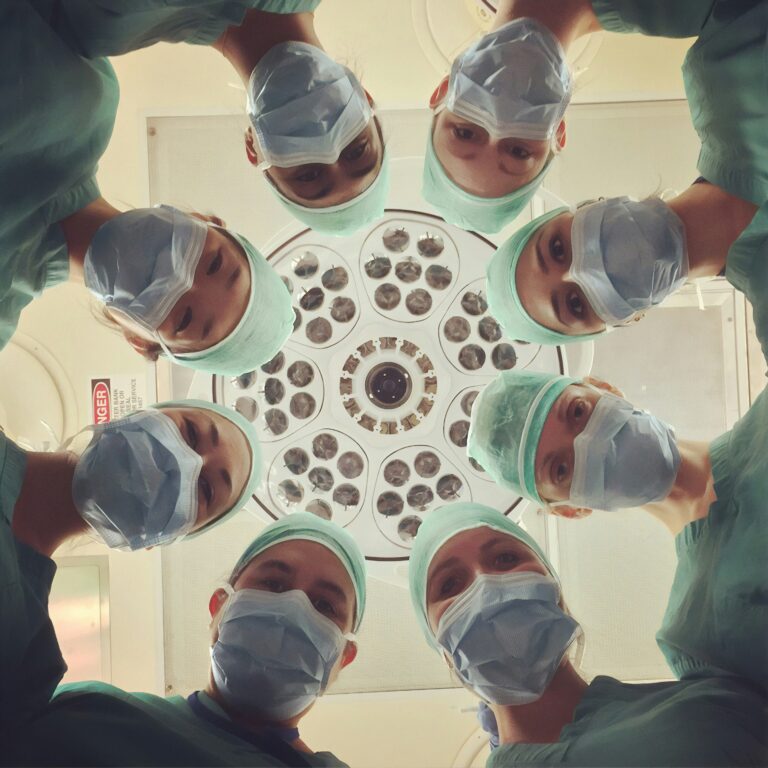

Anestezie: Bolest dostala utrum díky večírku

Bez anestezie byly dějiny chirurgie spíše dějinami bolesti. I když od starověku se prověřovaly nejrůznější způsoby, jak během operací docílit znecitlivění, nejběžnější praxí zůstávalo řezání do člověka při jeho plném vědomí. Bolest dostala utrum až díky večírku. V 19. století se mnohé večírky neobešly bez nehořlavého plynu s nevýraznou vůní a nasládlou chutí. Zábava s oxidem […]